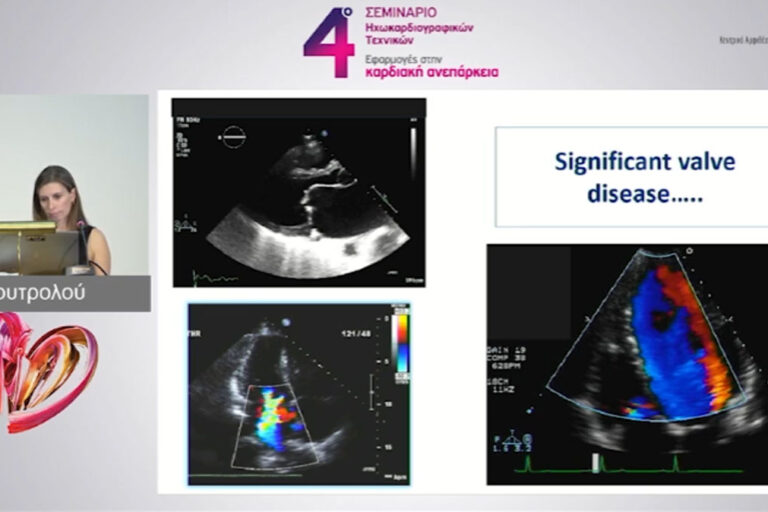

4ο ΣΕΜΙΝΑΡΙΟ ΗΧΩΚΑΡΔΙΟΓΡΑΦΙΚΩΝ ΤΕΧΝΙΚΩΝ – ΕΦΑΡΜΟΓΕΣ ΣΤΗΝ ΚΑΡΔΙΑΚΗ ΑΝΕΠΑΡΚΕΙΑ

ΣΤ. Επείγουσα (FoCUS) υπερηχογραφία Χρήση από καρδιολόγους και άλλες ειδικότητες